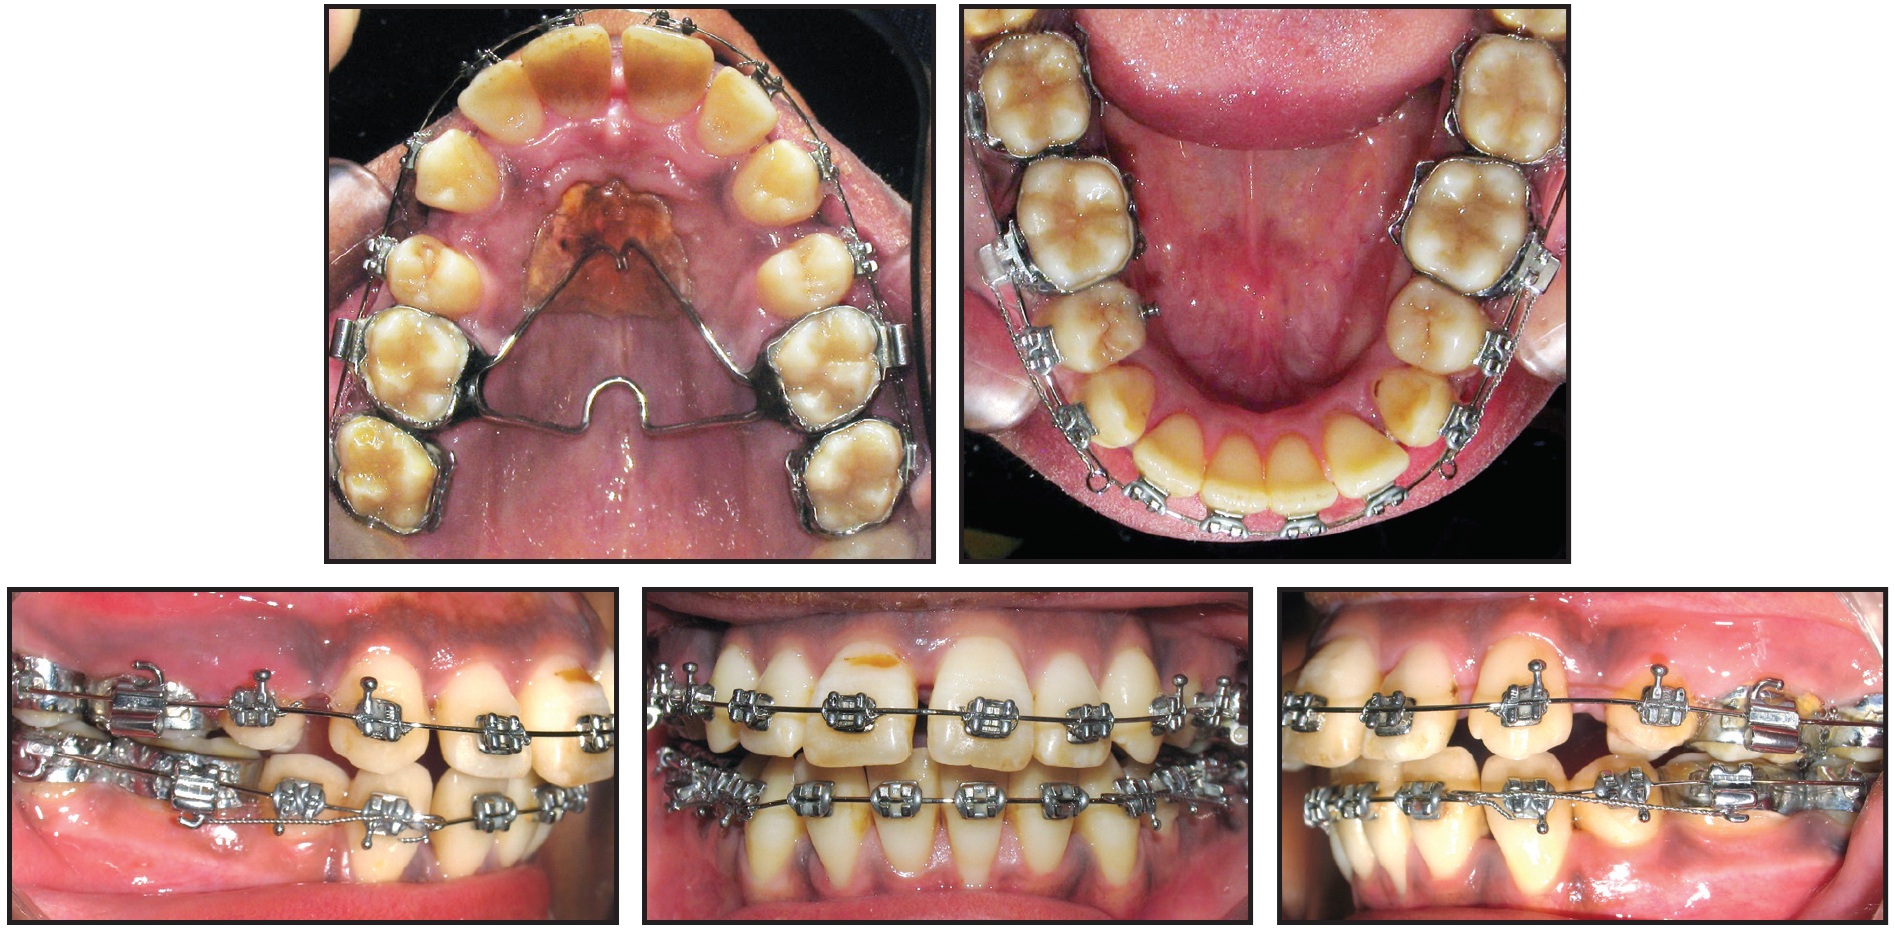

Another month later, the four first premolars and the supernumerary lower premolar were extracted. Double J-hooks were placed mesial to the upper canines, lower right canine, and left second premolar for derotation and to create space for the left canine (Fig. 2). The patient was instructed to wear the J-hook headgear 10 hours per day for distalization of the upper and lower canines.

Fig. 2 Nance appliance and transpalatal bar cemented to upper first molars and .022" × .028" Roth-prescription preadjusted edgewise appliance bonded in both arches, bypassing upper incisors, with .018" stainless steel archwires bent passively to fill bracket slots. After extraction of four first premolars and supernumerary lower premolar, double J-hooks placed mesial to upper canines, lower right canine, and left second premolar for derotation and to create space for left canine.

Fig. 3 After four (A) and seven (B) months of treatment.

After 11 months of treatment, enough space had been created to bond the upper incisors. An .014" nickel titanium overlay wire was placed, followed by an .018" nickel titanium and continuous .018" stainless steel archwires.

After 17 months of treatment, retraction of the upper anterior teeth was begun with closing-loop mechanics, using an .017" × .025" stainless steel archwire (Fig. 4).

Fig. 4 After 17 months of treatment, retraction of upper anterior teeth initiated with closing-loop mechanics using .017" × .025" stainless steel archwire.